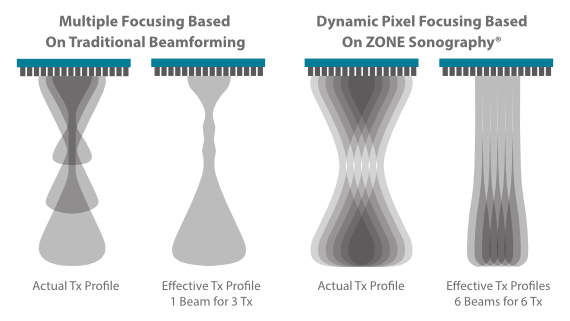

MX7? ??? ZST+ ???? ???? ??? ??? ???? ?? ??? ?? ??? ??? ??? ?? ???? ?? ???? ?????? ?????. ??? ?? ??? ?? 8??? ??? ??? ?? ?? ??? ?? ???? ??? ?????. ?? ?? ? ?? ??? ?? ??? ??? ? ????.